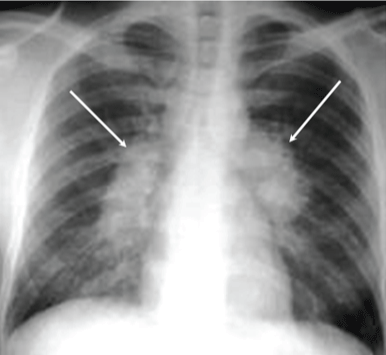

Active TB

Latent TB

Primary Infection: On first infection, individuals are more likely to have rapid onset of severe disease and are at higher immediate risk of death.

Secondary Infection: On subsequent exposures, individuals are less likely to develop disease quickly and those that do may have longer-term, chronic infections.